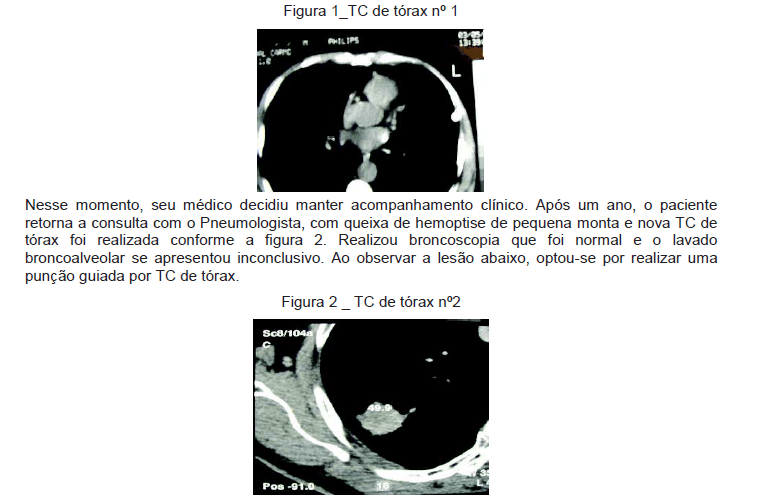

Homem de 75 anos, há 20 anos com tosse seca, sibilância e dispneia progressiva. Ocasionalmente tem tosse produtiva com expectoração mucóide. Em uso de aerossol com a associação salbutamol e ipratrópio. Ex-fumante há três anos, tendo fumado dos 12 aos 72 anos de idade (90 anos/maço), pai falecido com câncer gástrico. Realizou a TC de tórax nº 1, conforme figura 1.

Em relação às TC de tórax apresentadas nas figuras 1 e 2, é correto afirmar que